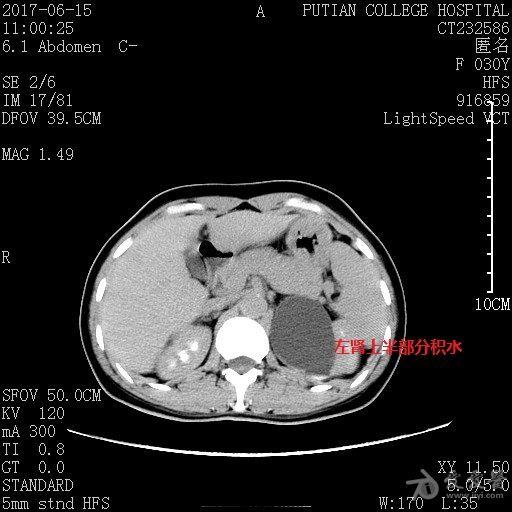

双侧肾盂输尿管重复畸形并肾积水1例

ctu双肾盂畸形并上肾盂积水,肾盂旁囊肿